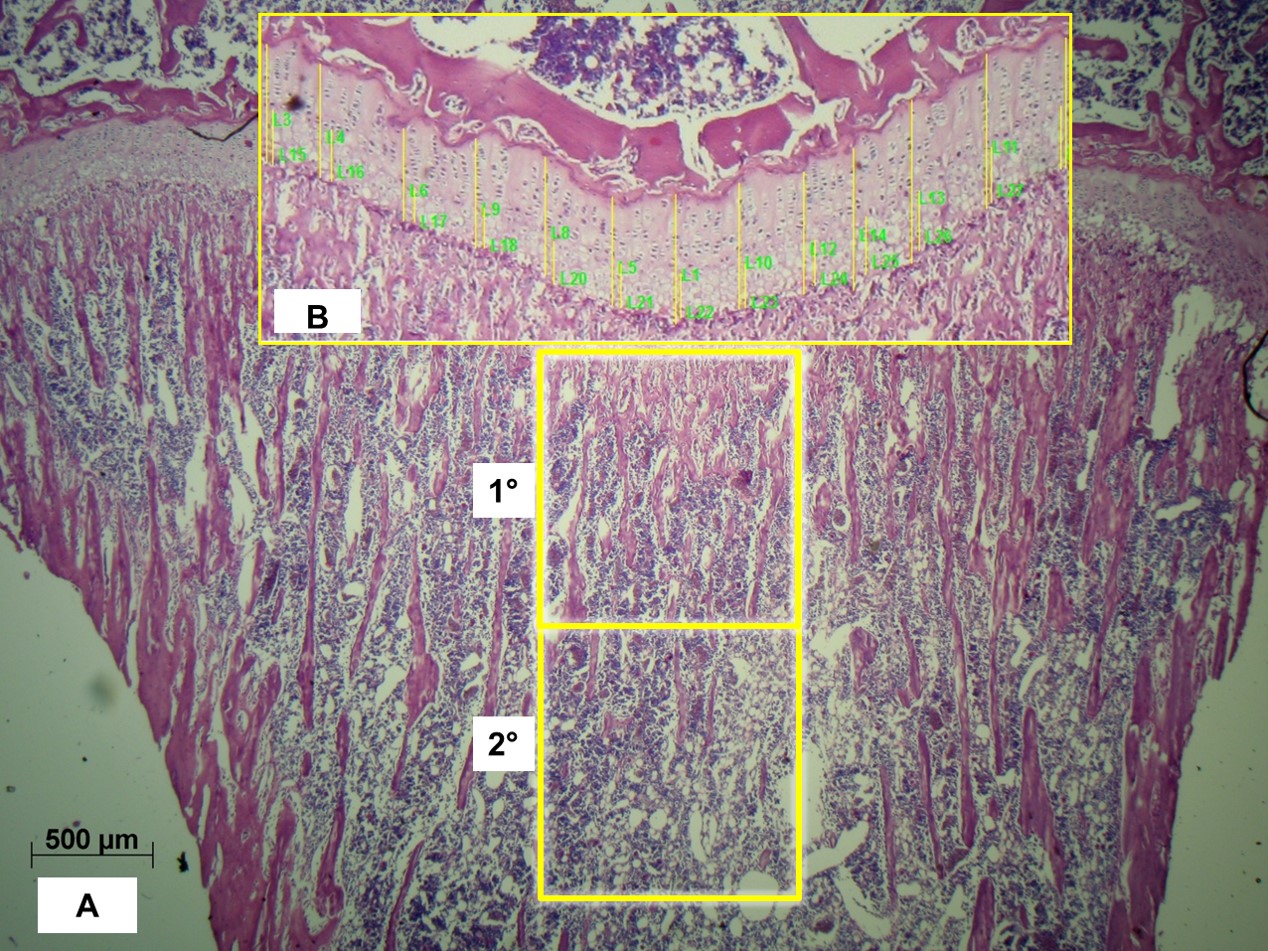

On digital microphotographs, with the Image Pro Plus 2.0 program, the bone volume as a percentage of total bone volume (BV/TV%) of trabecular bone in the tibiae was determined on the central area of subchondral bone. Histomorphometric measurements were divided in primary (BVA/TVA%) and secondary (BVB/TVB%) cancellous bone (Figure 3A). Also, thickness of growth plate cartilage (GPC.Th) with its hyperthrophic zone (HpZ.Th) was determined as the mean of thirteen independent records (Figure 3B).

Figure 3: Digital micrographs of tibiae in longitudinal section, H & E A: Bar equivalent to 500 μm. Boxes show regions of primary (1°) and secondary (2°) cancellous bone. 25X. B: Ephiphyseal cartilage analyzed by image pro plus. Bars indicate 13 repeats of GPC. Th and HpZ. Th. 125X. View Figure 3

No significant histomorfometric differences (p > 0.05) were encountered in total bone volume, nor in primary or secondary cancellous bone areas (Figure 7, Figure 8 & Figure 9A). The same occurred in thickness of growth plate cartilage and its hyperthrophic zone (Figure 9B).

Figure 9: A) Digital micrographs of tibiae in longitudinal section, H & E 125X of control (C) and experimental (E), primary (1°) and secondary (2°) cancellous bone. B) Digital micrographs of tibiae in longitudinal section, H & E 125X of control (C) and experimental (E), ephyphyseal cartilage. View Figure 9